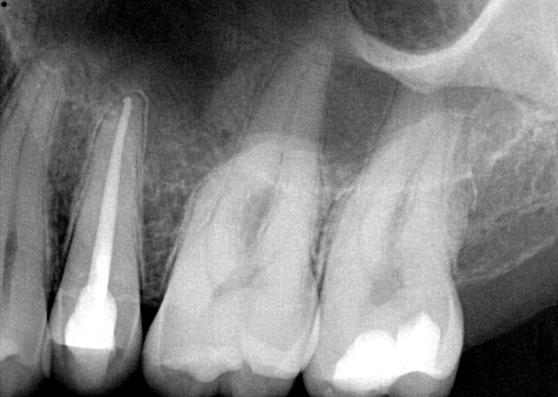

Fig 8. Gold crown removed, dentin excavated, canals shaped and filled.

Figure 8

The patient returned for final evaluation of the provisional calcium-hydroxide endodontic therapy and resolution of the infection (33 days postoperatively). Fistula was not present; the tooth was not sensitive to percussion or mastication. The gold crown was removed using a high-speed metal cutting bur, the remaining caries were excavated conservatively, and the endodontic therapy was completed. Placement of glass-fiber reinforced composite and composite core buildup took place. The natural tooth structure to receive the glass-fiber post and a long-term restoration was available (Figure 8). Within one appointment, the tooth was restored (Figure 9). The patient was instructed to return for clinical and radiographic evaluation after 6 to 12 months to determine progression of periodontal healing. At that time, if the healing were adequate and the tooth were stable, evaluation of the tooth would be considered every 3 to 4 years.7